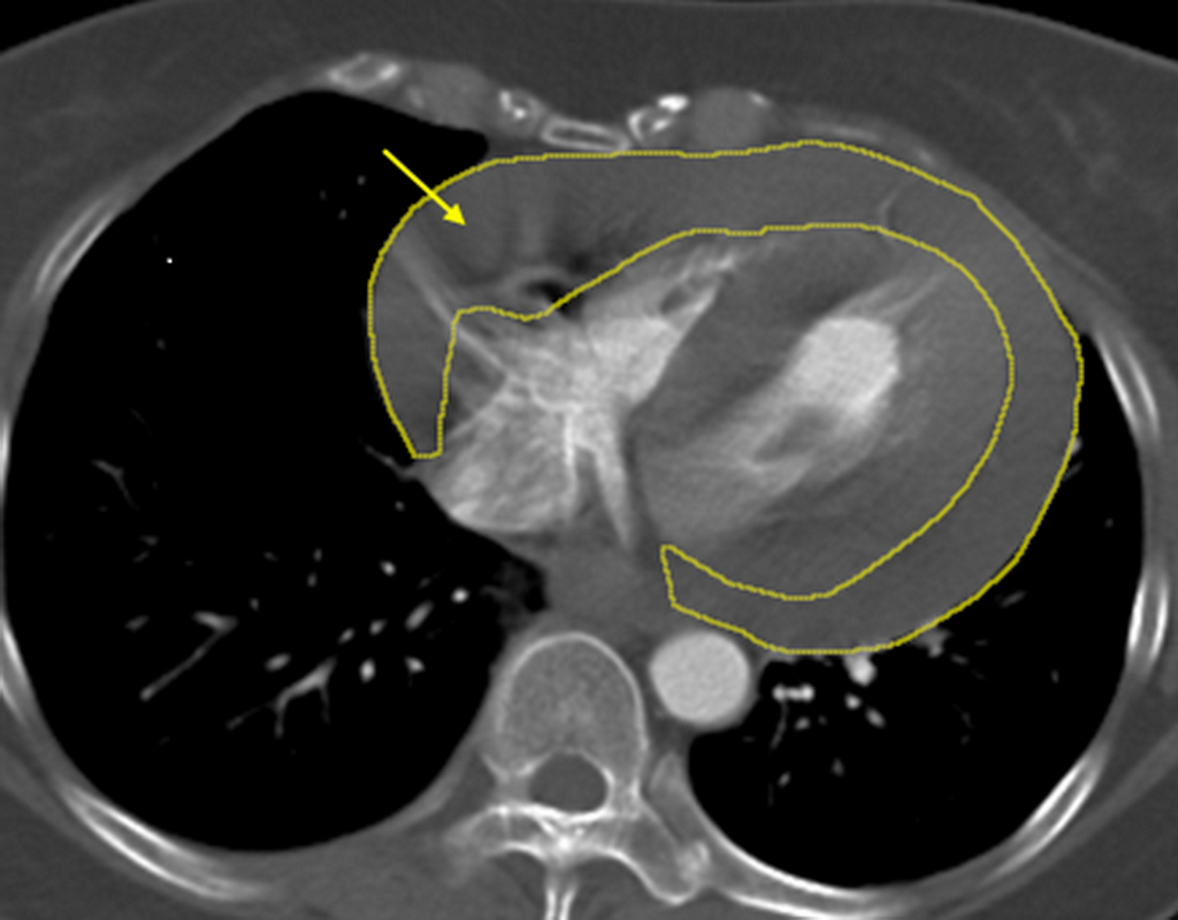

針對陳女這次暈倒休克,經影像檢查確認為大量心包積血,醫療團隊第一時間成立跨科搶救小組,由心臟外科緊急執行「劍突下心包開窗術」,迅速解除心臟壓迫、穩定循環;隨後無縫銜接由血管外科進行高難度的「升主動脈置換術」,以人工血管重建破裂的主動脈。在術後並陸續完成止血、調整及胸骨固定等關鍵處置,終於順利挽回陳女一命。